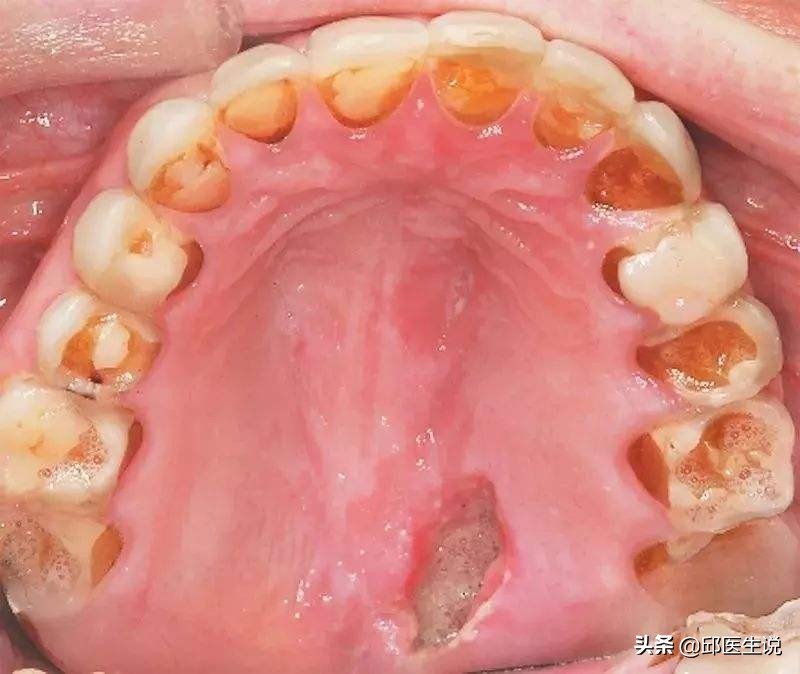

胃酸的腐蚀性较强,催吐时,食物和胃酸沿着食道和口腔流出,反复腐蚀经过之处。

就连牙齿,作为人体最坚固的部位之一,都不能幸免。

若长期催吐,牙齿被胃酸反复腐蚀,就会造成不可修复的严重牙齿损伤,而且就算催吐后刷牙也无济于事。另外胃酸和扣喉都会伤害到喉咙,经常催吐的人常常会觉得喉咙疼痛无力,声音嘶哑,若是被指甲刮损出现创面,极易感染。